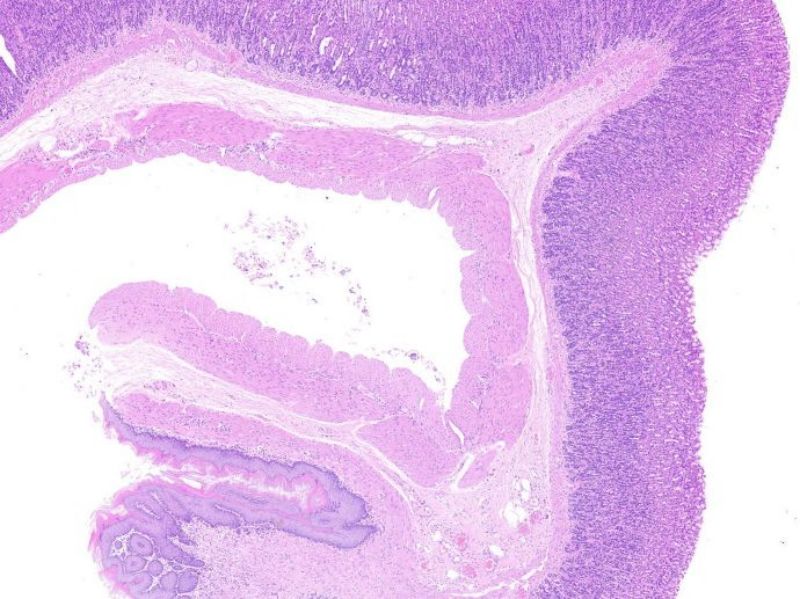

炎症性肠病动物模型

结肠直肠癌动物模型